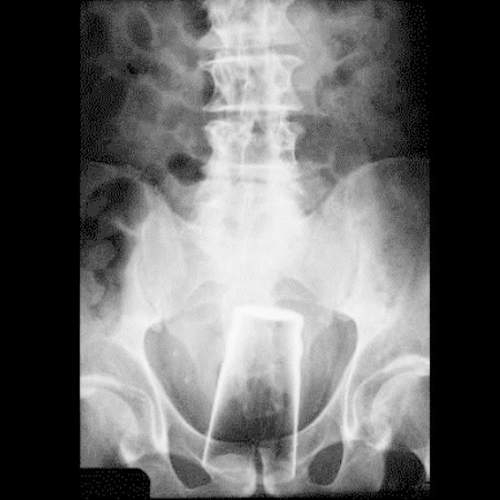

電動蘇格蘭也是異物突入X光照當中的人氣品項,不過這張照片特別的地方是...當一根電動蘇格蘭卡進去的時候該名男子又用了沙拉鉗來夾蘇格蘭,結果雙雙卡在裡面...